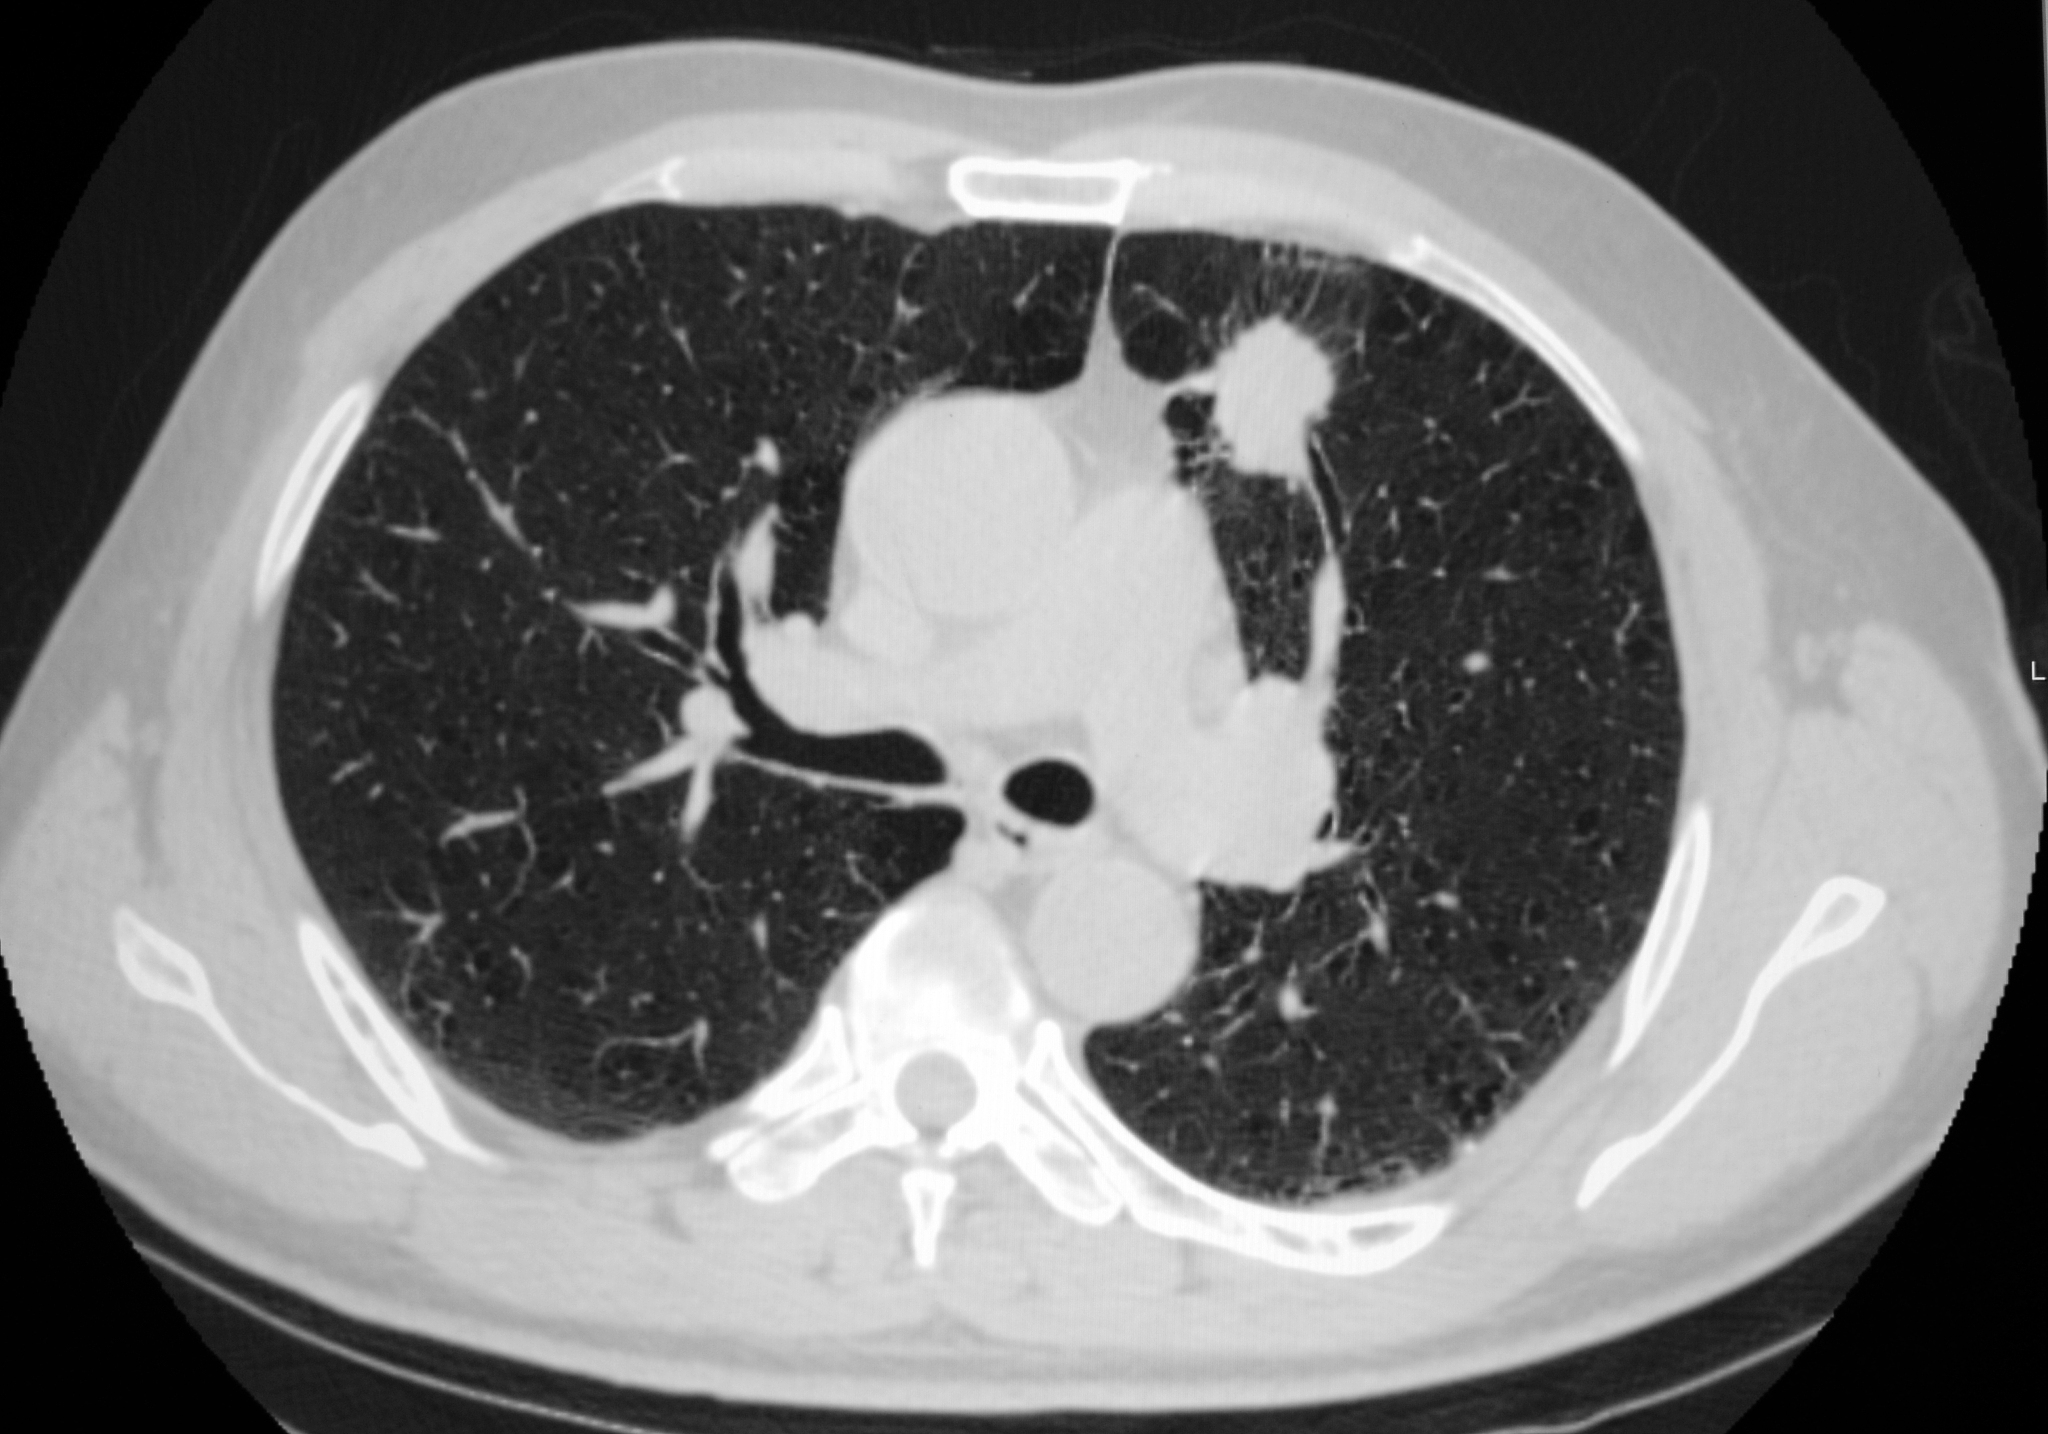

“白肺”也叫急性呼吸窘迫综合征(ARDS),一般指重症肺炎患者在X光或CT检查下的表现,肺部显影呈一大片的白色状而得名。临床表现为胸闷气短、呼吸不畅,白肺患者的血氧饱和度较低,因此会导致严重缺氧的结果。